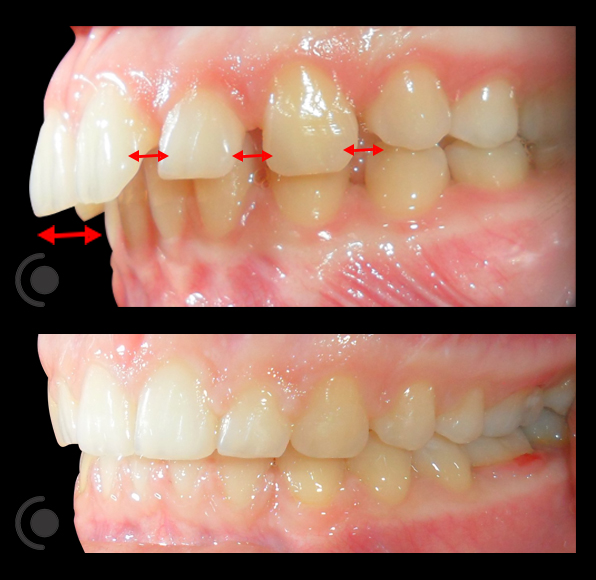

O našoj kvaliteti najbolje govore naši rezultati!